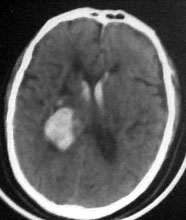

病人男性52岁,一年前曾患脑出血.今突发剧烈头痛,恶心,呕吐..病人家属说病人自去年脑出血以后,精神异常!请大家看看左侧颞叶病灶考虑什么?片子不是很清楚请大家见谅!!左颞叶病灶ct值最高处为85hu

左侧颞叶海马回钩部斑片状高密度致密影,考虑:出血.

病人此次症状应与右侧丘脑及基底节出血破溃入脑室有关。

左颞叶病灶我认为不是出血,就算是出血,也与右侧病灶性质不同。理由:1.该病灶密度较淡而不均匀,其间见斑点状更高密度。急性出血,应该不会是这个样子。

2.病灶对周围无推移挤压迹象,也无水肿。倒是病灶旁边、左侧环池局部扩张,与右侧病灶

完全不一样。

综合上诉特点,左颞叶病灶我首先考虑:avm。

左侧颞叶考虑血管畸形,右侧丘脑及基底节出血破溃入脑室

考虑1海绵状血管瘤。2脑膜瘤待排。建议增强

左颞叶病灶我认为不是出血,因为边界不清,无水肿带,应该是散在钙化灶,不排除avm,建议增强.

左侧颞叶病灶密度不均,似见点状钙化,支持血管畸形性病变.右侧病变为出血.